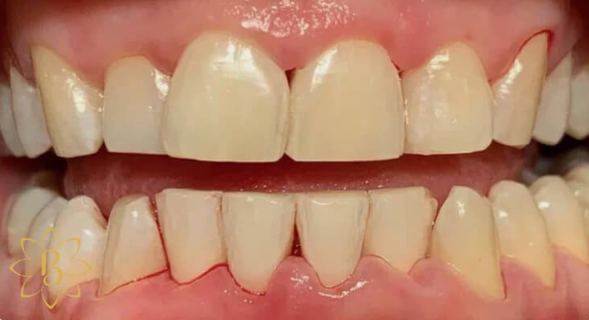

На странице представлено портфолио стоматологий Санкт-Петербурга с работами до и после профессиональной чистки зубов. В нашем портфолио собраны разные клинические случаи: от удаления незначительного налета до снятия массивного поддесневого камня. Здесь вы можете увидеть, как возвращается естественный цвет и внешний вид зубов после процедуры. Изучите результаты до и после чистки зубов, чтобы увидеть реальный эффект и выбрать клинику в Санкт-Петербурге, где профессиональная гигиена поможет вернуть зубам здоровый вид.

Профгигиена